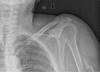

Fractura impactada de húmero .